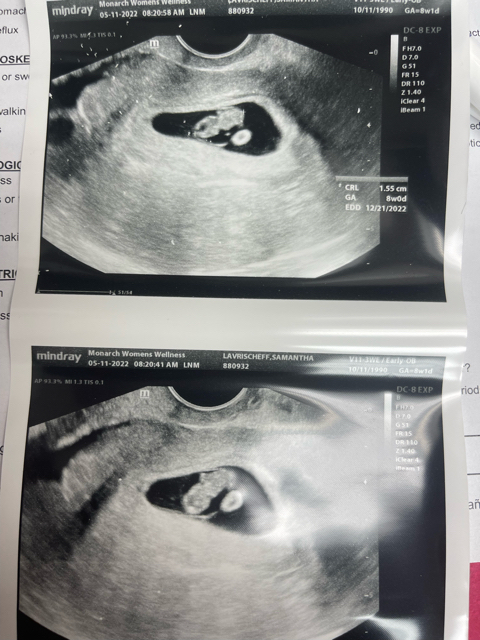

8 weeks 1 day!

Little boy is right on track! Had a blood test to determine early gender. We decided we already “secretly” told enough people that we made it official. 🤣